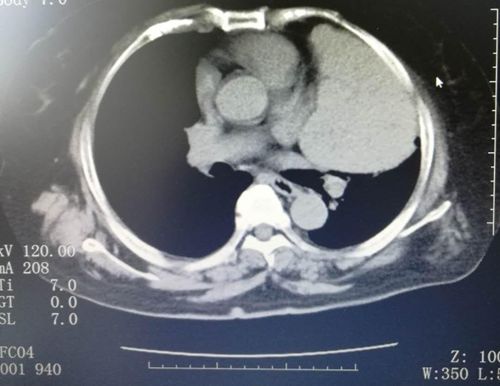

病人的影像检查

胸部X线是发现和诊断纵隔肿瘤的重要手段,可显示肿瘤的部位、密度、外形、边缘清晰光滑度、有无钙化或骨影等。透视检查,断层摄片、CT检测或核磁共振能进一步进行鉴别。